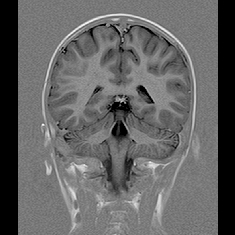

脳血管疾患や脳腫瘍などの脳疾患の有無を調べる検査として、一般的に、頭部CT、MRI、MRAと頸部MRA、頸動脈エコーなどが用いられています。

① MRI

② MRA

① 頭部

②頭部・頸部